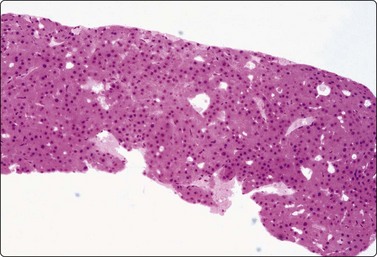

Tissue fragments and cell blocks

Sometimes, a thin core or fragments of tissue may be obtained with a standard 22-gauge needle (Fig. 2.14). Tissue fragments are fixed in 5–10% buffered isotonic formalin and processed as for routine histology.

image

Fig. 2.14 Tissue core by 22-gauge lumbar puncture needle

Tissue section of a 22-gauge lumbar puncture needle core from a well-differentiated hepatocellular carcinoma (H&E, LP).

Some laboratories recommend the routine preparation of cell blocks for paraffin embedding of FNB samples. Cell blocks may give a better idea of tissue architecture and allow multiple sections for panels of immune markers with controls.19-21 However, they are relatively time consuming and costly compared to routine smears.22 We use cell blocks selectively, mainly if a need for immunocytochemistry is anticipated. Cell blocks are helpful if samples are heavily admixed with blood. Surprisingly good tissue fragments are often found in a cell block even when smears show only blood.